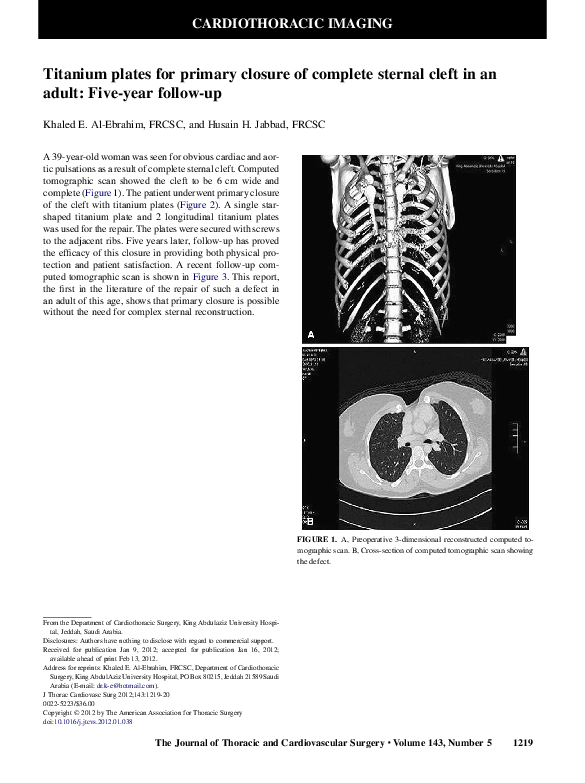

(PDF) Titanium plates for primary closure of complete sternal cleft in an adult Fiveyear Titanium Plate For Heart Surgery — sternal plate fixation is a risingly accepted method of sternal closure following cabg surgery; Sternal closure traditionally involves use of stainless steel wires with. Our wire and cable systems offer alternatives for sternal closure following sternotomies. interested in wire or cable closure? — different devices have been used to provide a more rigid fixation to avoid. Titanium Plate For Heart Surgery.